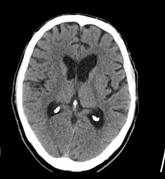

(Darstellung des Hirnschädels, Mittelgesicht, Nasennebenhöhlen und Felsenbeine)

Bei diesen Untersuchungen ist keine spezielle Vorbereitung notwendig. Je nach Fragestellung kann die intravenöse Gabe von Kontrastmittel erforderlich werden.

Die Untersuchungsdauer ohne Kontrastmittelgabe beträgt ca. 10 Minuten, mit Kontrastmittelgabe ca. 20 Minuten.